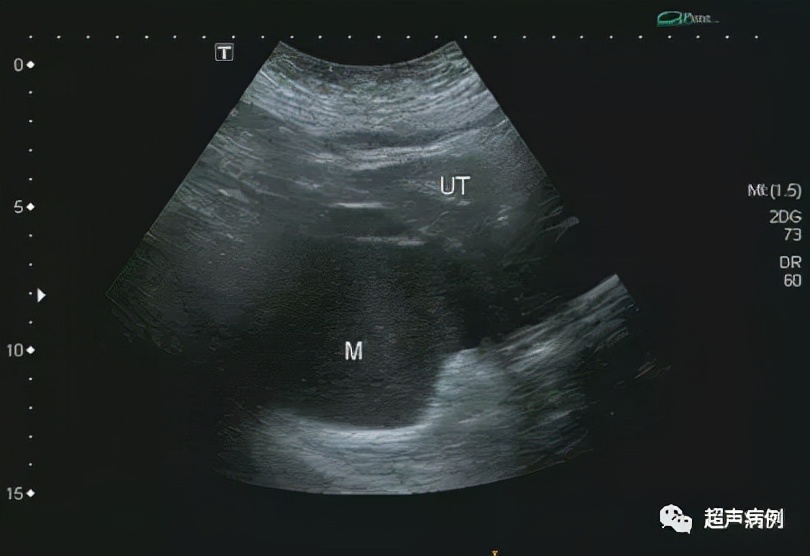

在子宫后方盆腔内查见一约10.4x9.7x7.3cm无回声区

形态规则,边界清楚,内透声差,呈毛玻璃样改变

内可见强回声分隔

CDFI:该无回声区内部及周边未见明显血流信号。

病理诊断:卵巢囊性成熟性畸胎瘤